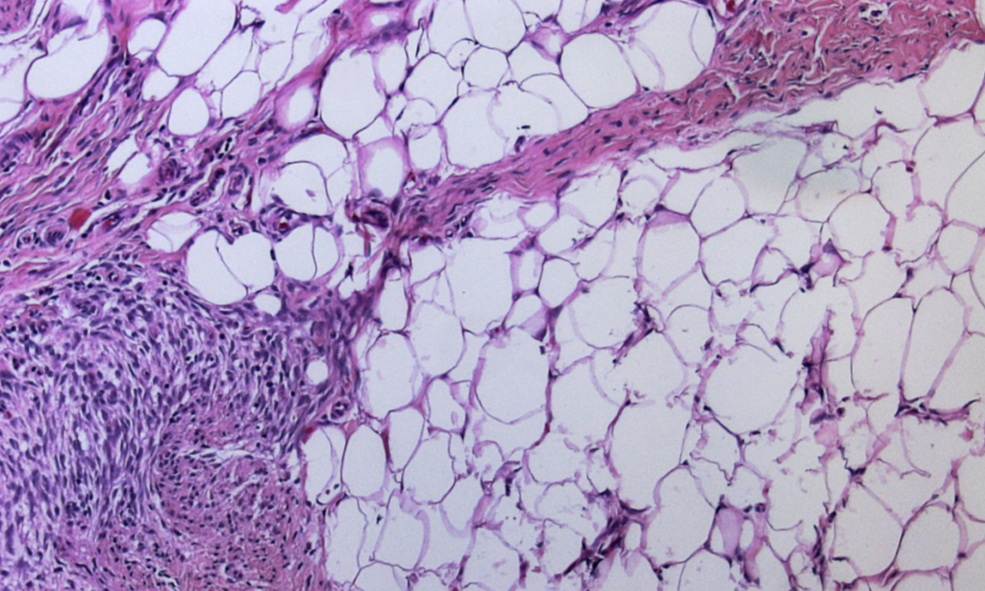

The microscopic appearance of the specimen was cellular collagenous connective tissue with isolated glands and multilayered ductal epithelia. The preparation contained some nerve fibre portions but no neurofibroma. Final histological diagnosis was a partially fibrosed mammary gland without any finding indicating neurofibroma. Considering the clinical presentation of the child, diagnosis was gynaecomastia (Figure 4 [Fig. 4]).

Figure 4: Representative microphotograph of excised breast tissue reveals fat tissue with fibrosis.